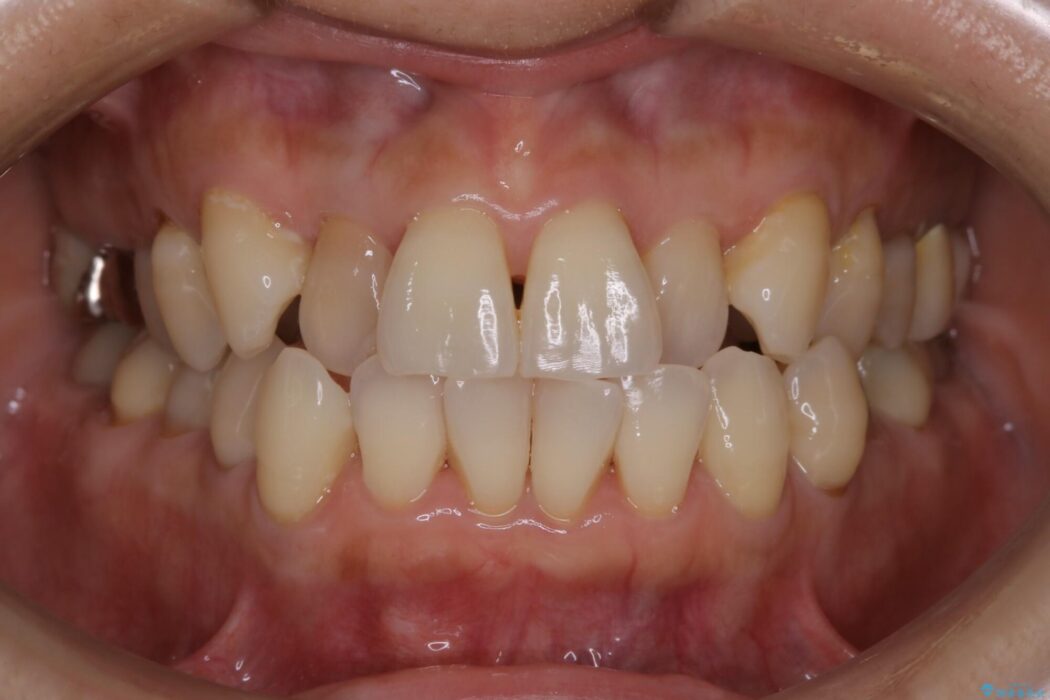

前歯のガタつき、噛み合わせの不調を改善したいとご来院されました。

全体的に歯列が狭窄しており、本来外側に覆いかぶさっている上の前歯が内側に入り込んでいました。

歯列弓全体の形状を整えるとともに歯の大きさもコントロールすることで非抜歯にて矯正を行いました。